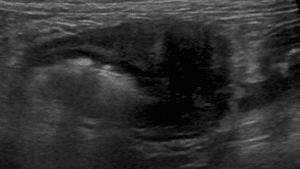

リンパ腫、乳腺腫瘍、肥満細胞腫などの腫瘍性疾患から、腎不全、尿路結石、膀胱炎、前立腺疾患などの腎泌尿器疾患まで、専門的な知見に基づいた診断と治療をご提供します。大切なご家族の病気に専門医が寄り添い、最適な治療をご提案できるよう努めてまいります。

腫瘍科外来

犬・猫のリンパ腫、乳腺腫瘍、肥満細胞腫などの腫瘍性疾患の診察と治療を行います。